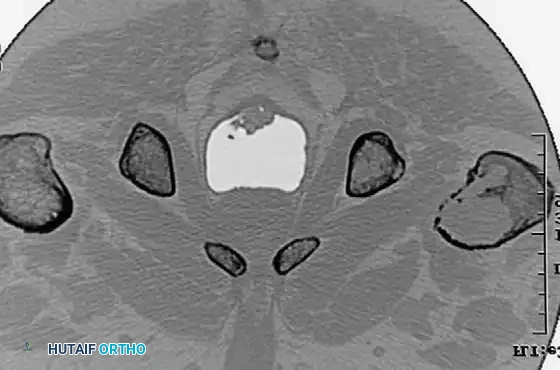

Image

CT scans demonstrating the extensive cortical destruction of the lesions, highlighting the imminent biomechanical failure and the absolute need for prophylactic fixation.

For extensive lytic lesions of the proximal femur (as seen in the provided CT scans), prophylactic stabilization is indicated to prevent catastrophic fracture.